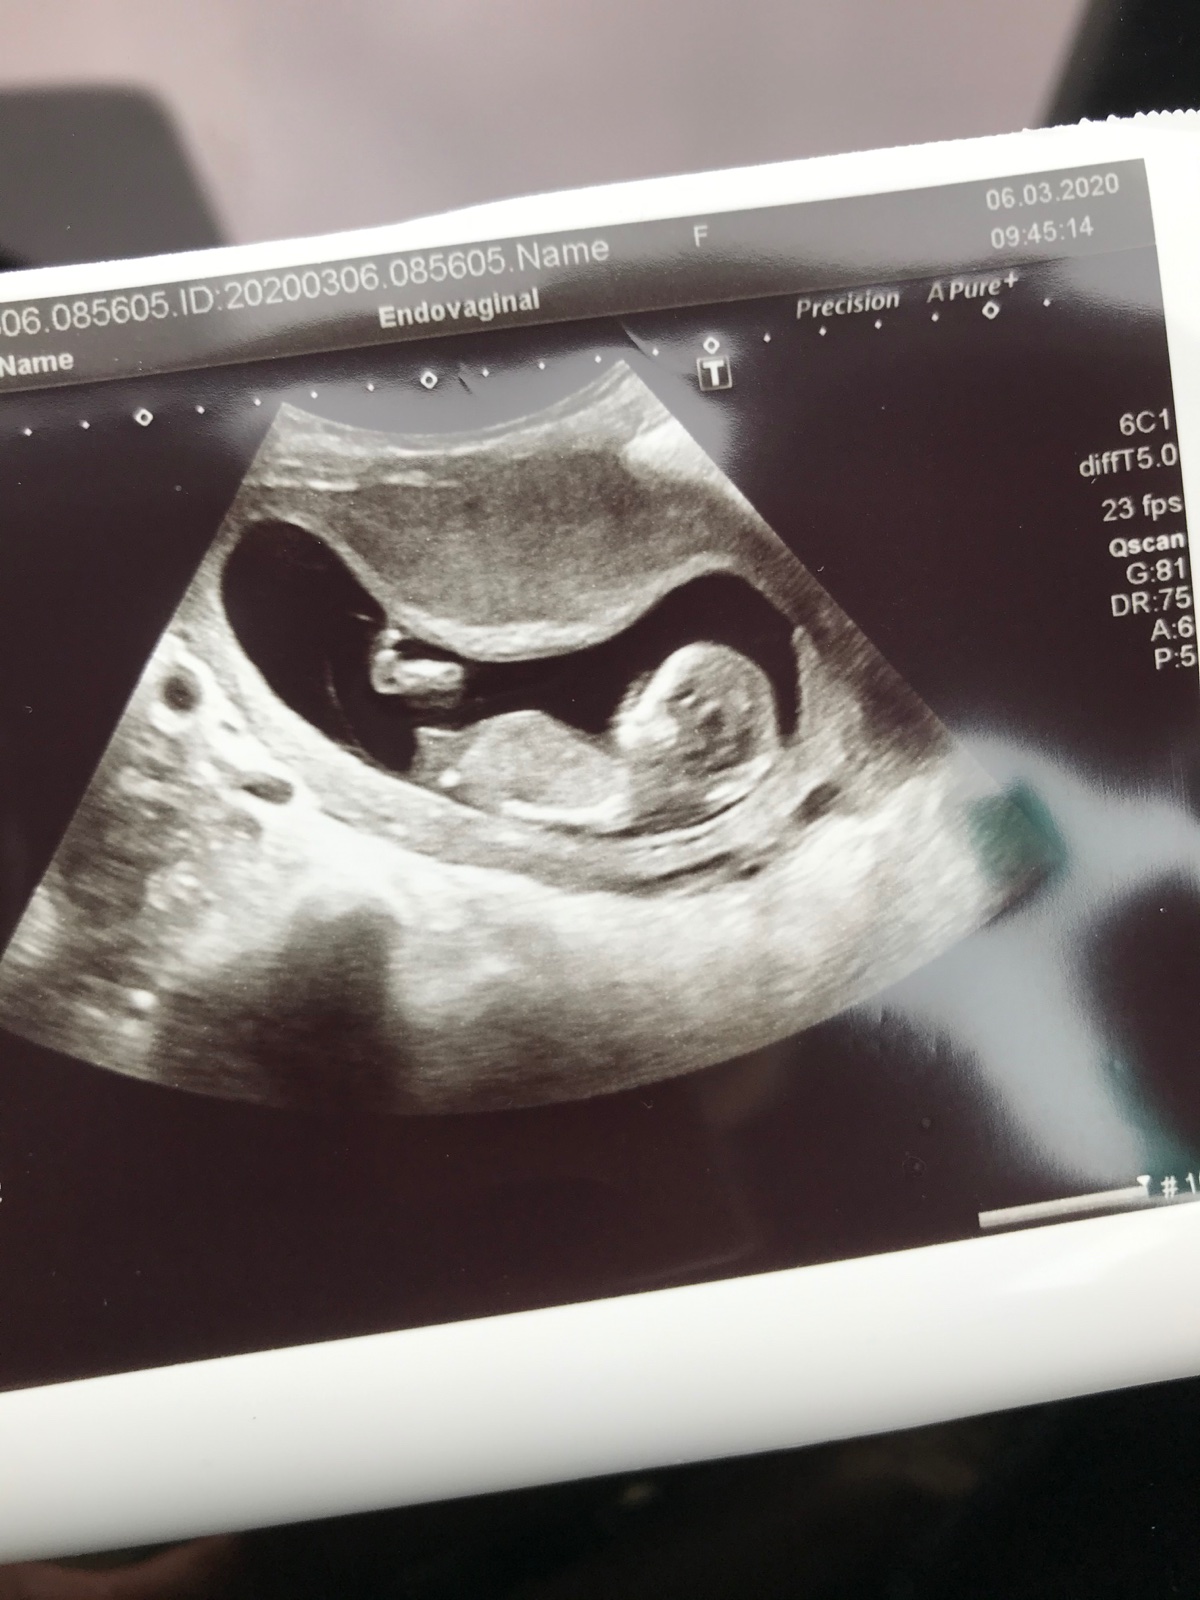

@sebinka123 Já soudím podle sebe 🙂. Když jsem byla se synem na screeningu prave 13+2, tak tam ten hrbolek šel kolmo nahoru jako takový čudlik :D. U druhého syna jsem byla o 2 týdny dřív (11+0) a tam to vypadalo spis na holku, ale to bylo tim, ze to bylo moc brzy ;). Za ty 2 týdny uz by to určitě bylo jasnější 🙂. Tak potom dejte vedet. Sama jsem zvedava. Jinak opravdu zavidim těm, co to vydrží si to nenechat říct 🙈. Já jsem to nevydržela ani u jednoho a trochu me to mrzí, ze jsem taková zvedava 😂. Říkám, ze kdyby bylo třetí, tak určitě nechci vědět, ale jak se znam... Tak to zase nevydrzim 🙈

@sebinka123 Já si myslím, že u Vás ten hrbolek je holčičí, na ten týden, kdy jste byla, by byl kluk víc nahoru a šikmý. Z té fotky, kde to vidím, miminko sice neleží úplně rovně, ale já si myslím, že to bude holka. My jsme vydrželi si neříct i u druhého, někdy to jsou nervy :D Ale při porodu to je pak zážitek 🙂 Já něco poznám z ultrazvuku, ale dokud to není oficiálně od dr., tak to beru jen jako můj tip ;) K tomu na tom ultrazvuku je to rychlé a vidíte jen chvilku něco, oproti fotkám, které máte v ruce a můžete zkoumat 🙂 Jinak já tohle těhu mám po tom 3. měsíci jiné, předtím mi bylo špatně jako s kluky, ale myslím, že to bylo teď méně a těhu nevolnosti už netrvají, kdežto s kluky ano a musela jsem furt jíst. Ale na tohle já moc nevěřím. My jsme třetí chtěli, i kdyby předtím byl páreček, ale teď by ta holka teda byla super :D

Holky vidíte něco tady ? je to ta menší fotka vlevo nahoře z Prenatalu ze 13.týdnu - z te celkove neni videt nic 🙂 nechali jsme si napsat do obálky od dr. Vlašína . V pondělí jdeme na druhý screening , necháme znova napsat pro jistotu a po něm už asi otevřeme (přítel to chce vědět 🙂 . Počítám od začátku tak nějak s klukem 🙂